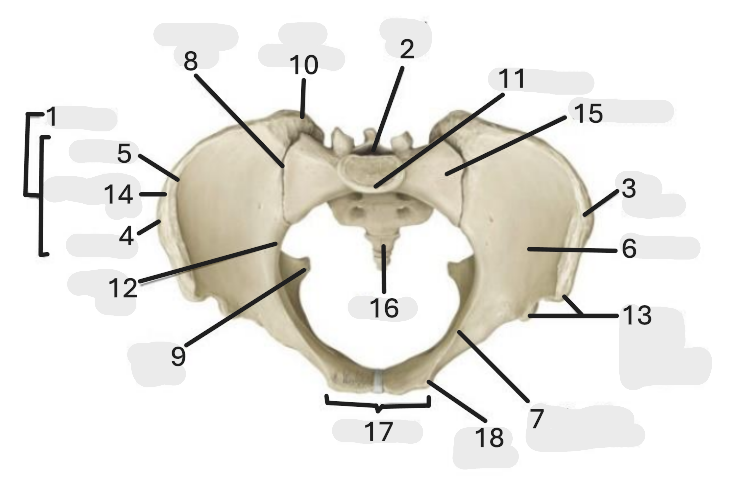

Where is the pelvic inlet

1

Where is the sacro-iliac joint

2

Where is the pubic tubercle

3

Where are the S1 body

4

Where is the ischial spine

5

Where is the ala of sacrum

6

Where is the anterior superior iliac spine

7

Where is the ischiopubic ramus

8

Where is the coccyx

9

Where is the obturator foramen

10

Where is the pubic symphysis

11

Where is the ischial tuberosity

12